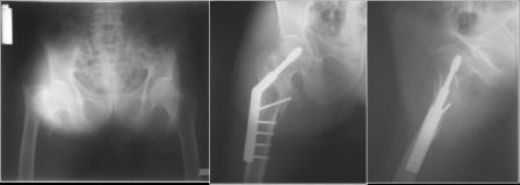

Pelvis Kemiği Önemi